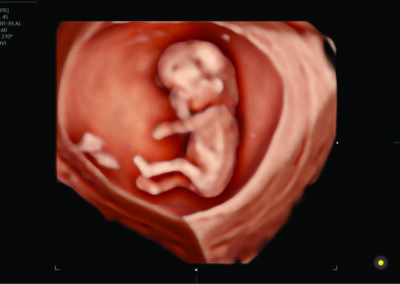

Comprehensive, advanced and expert MFM care for high-risk pregnancies